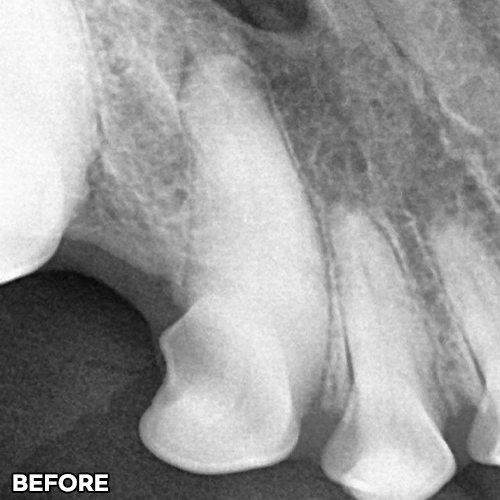

[강아지발치] 잇몸뼈가 녹은 구멍에 자기잇몸뼈가 튼튼하게 재생되어 채워졌어 - 강아지치아발치 2년 후 구강X-ray 비교! -

2025.11.26